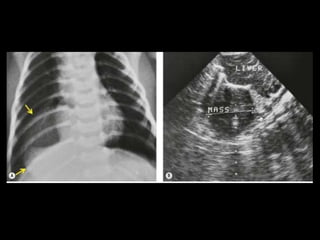

Nível hidroaéreo: leite de cálcio

Cisto Broncogênico(CB) É de longe a forma mais comum de cisto de duplicação do intestino anterior resultante de uma má separação ventral com a árvore traqueobrônquica; Cerca de 80% dos casos ocorrem nas regiões paratraqueal ou subcarinal; Os CB são malformações císticas congênitas dos pulmões raras e apenas de 10-30% apresentam localização intrapulmonar;

Cisto Broncogênico(CB) Todosos CB apresentam uma camada de epitélio respiratório e podem conter cartilagem; Caracteristicamente, os CB não se comunicam com a árvore traqueobrônquica até que se tornem infectados; Os CB n parênquima pulmonar podem estar associados à hiperinsuflação e ao aprisionamento aéreo, como resultado de um mecanismo de válvula ou atelectasia pós-obstrutiva.